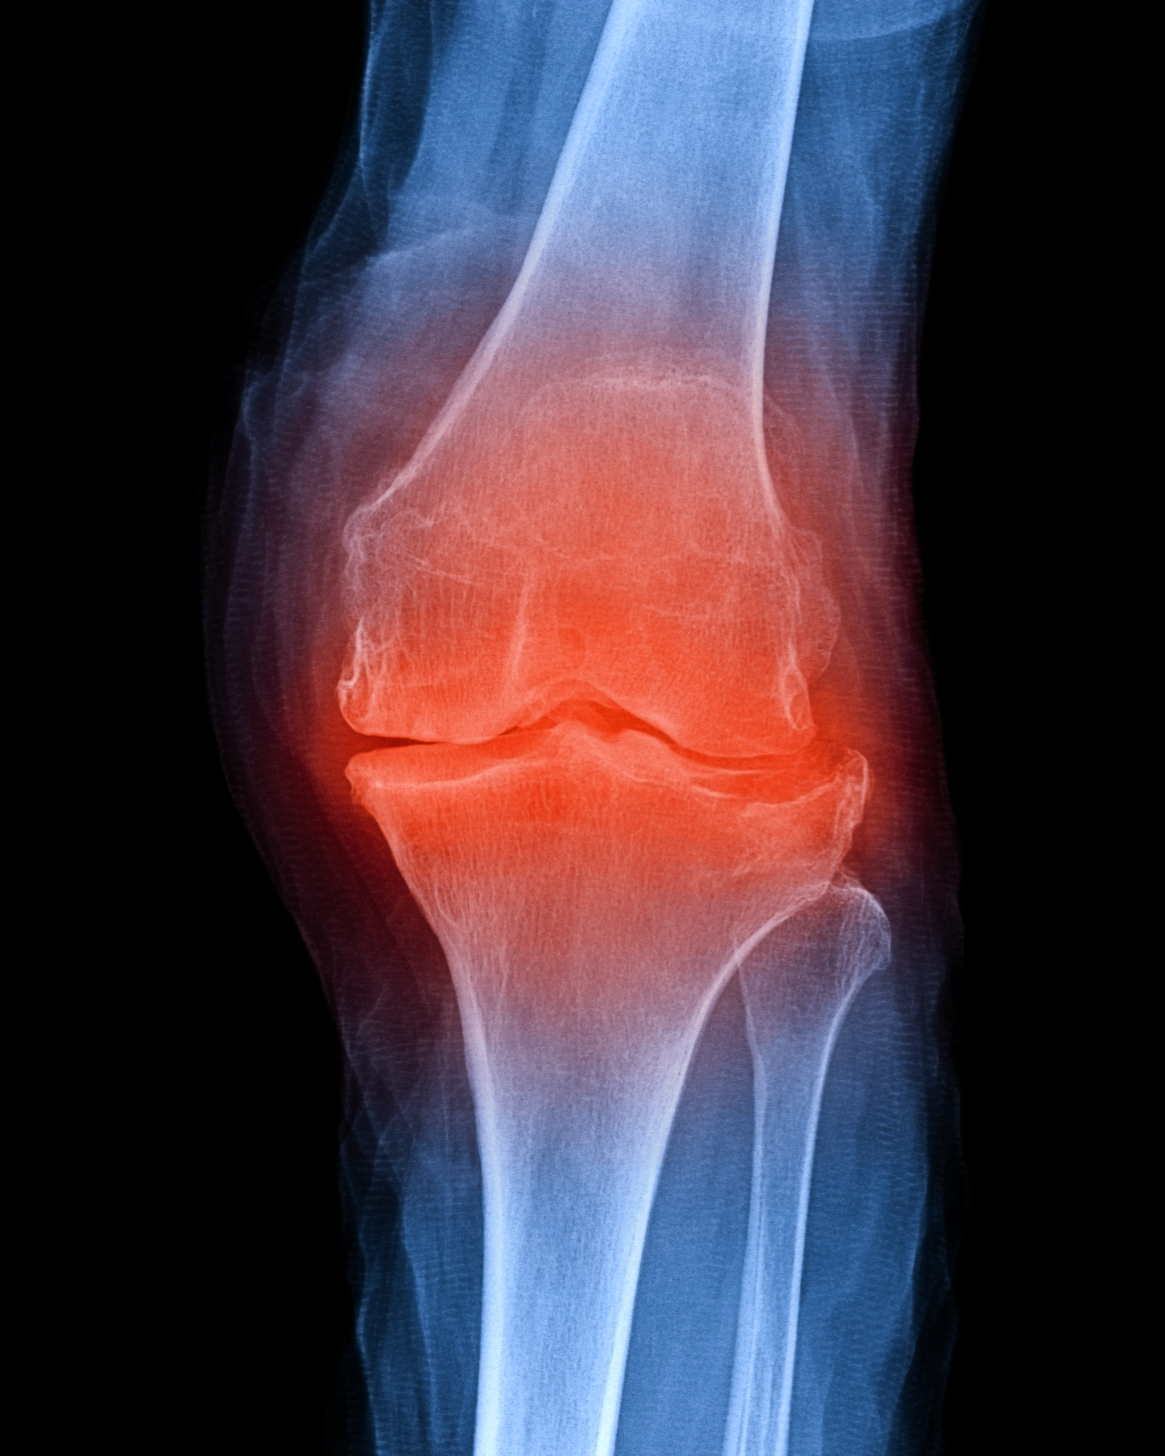

Kniegelenk – Aufbau, Arthrose und moderne Möglichkeiten zur Behandlung

Das Kniegelenk ist ein Dreh-Scharniergelenk. Durch die Verbindung von Oberschenkelknochen und Schienbein ermöglicht das Kniegelenk die Beugung und Streckung des Beins sowie eine leichte Drehung des Unterschenkels bei gebeugtem Knie.

Dabei besteht das Kniegelenk aus Knochen, Knorpel und Bändern. Das Zusammenspiel dieser Komponenten führt zu einem reibungsfreien Verlauf. Ist ein Teil dieser Komponenten gestört, kommt es zu Problemen und Schmerzen im Bereich des Kniegelenks.

Wie äußert sich eine Kniegelenkarthrose?

Eine Kniegelenksarthrose tritt in der Regel schleichend auf. Zunächst verspürt der Patient nur Schmerzen bei starker Belastung. Mit der Zeit werden die Schmerzen stärker und können auch in Ruhe auftreten. Typisch ist auch ein wechselhafter Verlauf. In den Anfangsphasen der Erkrankung sollte eine konservative Therapie durchgeführt werden.